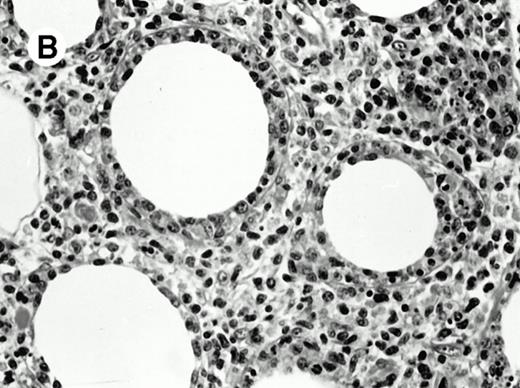

Three cases (cases no. 1 to 3) were located in the nasal cavity. The neoplastic infiltrate consisted of medium and/or large pleomorphic lymphoid cells (Fig 1)intermingled with variable numbers of small lymphoid cells, plasma cells, eosinophils, and histiocytes. Features of angiocentrism and angioinvasion, epitheliotropism, and areas of necrosis were observed in all three cases. Patient no. 4 presented with disease restricted to the lung and an open-lung biopsy was available. The neoplastic infiltrate was composed of large atypical lymphoid cells and was predominantly interstitial without extensive destruction of the normal architecture. Features of angiocentrism, angioinvasion, and epitheliotropism were present (Fig 2A and B). Case no. 5 involved the larynx, extending to the piriform sinus, the ventricle, and the arytenoid. One month later, the lymphoma disseminated to the subcutaneous tissue in the spinal region and biopsy specimens from both sites were available. The neoplastic cells were medium and large, with abundant clear cytoplasm and slightly irregular nuclei with dense chromatin. Epitheliotropism was present in the larynx mucosa. Small foci of necrosis and angiocentrism were seen without angioinvasion. Three patients presented with cutaneous disease. Cases no. 6 and 7 were comparable, as both histories started with necrotic subcutaneous nodules of the thigh, which on histologic analysis were characteristic of cytophagic histiocytic panniculitis without evidence of lymphoma (Fig 3A). Second excisional biopsies of cutaneous nodules obtained 7 and 5 months later, respectively, showed characteristic features of lymphoma in both cases (Fig 3B). However, in case no. 6, skin biopsy specimens showed an epidermotropic PML lymphoma extending to the dermis and the subcutaneous tissue, whereas in case no. 7, the neoplastic infiltrate consisted of a PSC confined to the subcutaneous tissue, admixed with benign histiocytes that showed phagocytosis. Patient no. 8 presented with recurrent skin lesions with spontaneous remission over a period of 10 years. The initial skin biopsies demonstrated an intense epidermotropic neoplastic infiltrate that extended to the superficial and deep dermis composed of atypical PML cells. All cutaneous cases displayed features of angiocentrism, but angioinvasion was observed only in case no. 6 and foci of necrosis in cases no. 6 and 8.

Subcutaneous γδ T-cell lymphoma (case no. 6). (A) Initial biopsy sample shows characteristic features of cytophagic histiocytic panniculitis without evidence of lymphoma cells; (B) second biopsy performed 7 months later demonstrates involvement of the subcutaneous tissue by a pleomorphic γδ T-cell lymphoma (hematoxylin-eosin stain).